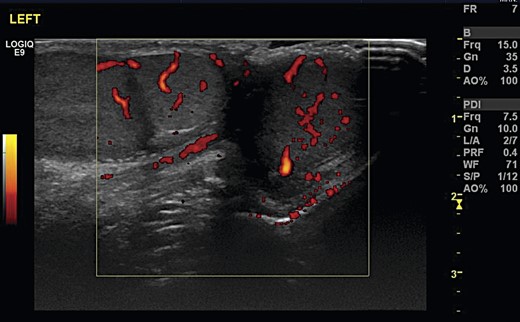

A 12-year-old boy was referred by his GP to the paediatric surgery clinic in a district general hospital with a 6-week history of a lump near the inferior pole of his left testicle. It was non-tender, non-erythematous and had not changed in size or consistency. He was otherwise fit and well, with no family history of urological disorders. On examination, his abdomen was soft and non-tender, with a normal right testis and right spermatic cord. A smooth well-defined lump was palpated on the inferior pole of the left testis. The rest of the testicle had a normal consistency with a normal left cord. Ultrasound demonstrated that both testicles were of a similar size, with normal vascularity and normal epididymi. The palpable lump corresponded to a well-defined 1-cm mass attached to the lower pole of the left testicle (Fig. 1). It had a similar echo pattern to the testicle with normal vascularity (Fig. 2), consistent with the finding of a bilobed testis.

Transverse ultrasonography of the scrotum. A mass is seen attached to the left testicle with the same vascularity as surrounding testicular tissue.